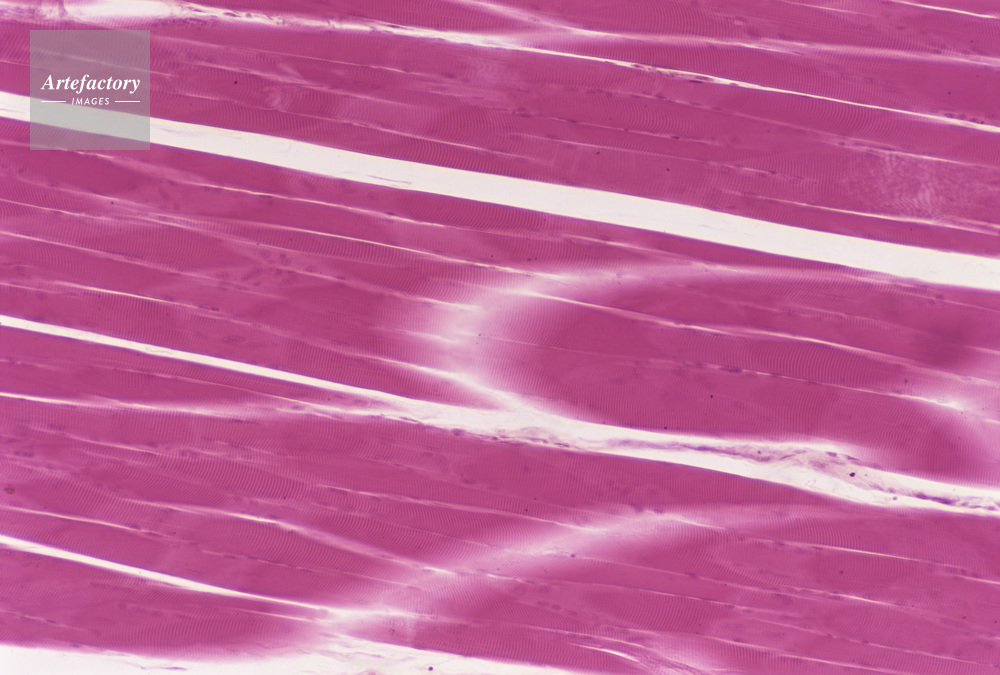

| 作品タイトル | 顕微鏡写真 | モデルリリース | なし | |

| キャプション | 人,人間,横紋筋,縦断面,断面 | 制限事項 | ||